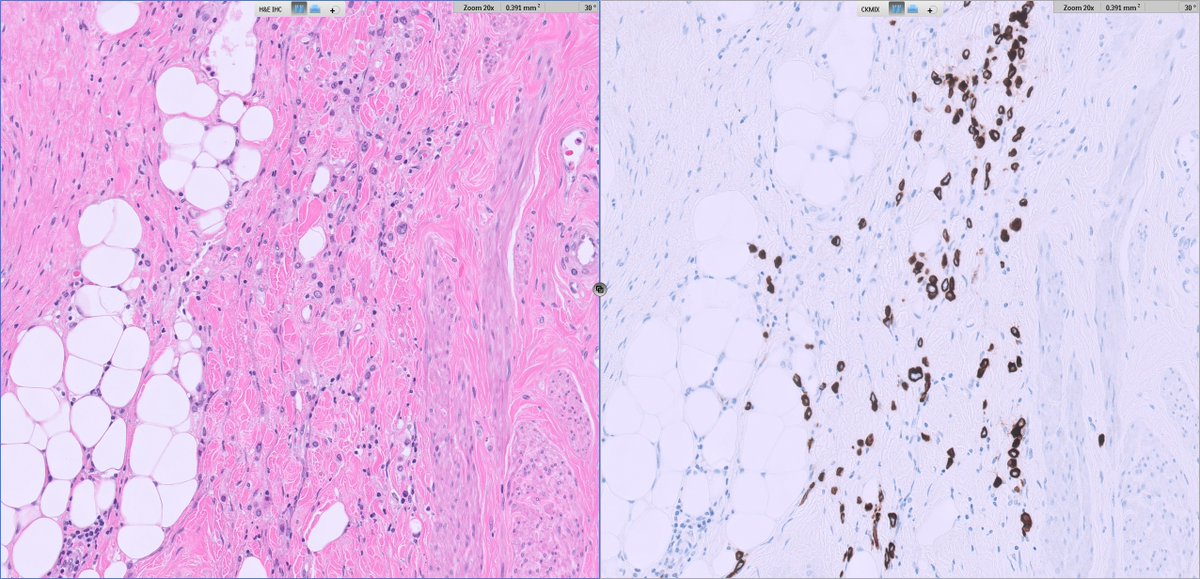

Architecture: grossly nodular tumors, but with infiltrative borders and “honeycomb” spread through subcutaneous fat and skeletal muscle.

Cytology: ovoid/epithelioid cells in cords, nests or solid sheets within dense collagenous stroma; mitotic activity usually low in hypocellular areas, higher in more solid/anaplastic foci.

Special patterns: perineurioma‑like areas (bland spindle cells in whorled/loose‑storiform pattern), fibroma‑like zones (very dense collagen with sparse cells), and foci of small round or rhabdoid cells in recurrences/metastases.

MUC4 consistently negative (key point against classic SEF/LGFMS)

Perineurioma/DFSP – honeycomb infiltration and CD34 expression may overlap, but they lack SEF‑like morphology and YAP1–KMT2A fusion.

Fibromatosis/scar – fibroma‑like areas may mislead; subtle atypia, transition to more cellular SEF‑like zones, and EMA/cyclin D1 expression favor sarcoma.

📌Consider YAP1::KMT2A‑rearranged sarcoma in SEF‑like/LGFMS‑like tumors that are MUC4‑negative.

MUC4 negativity + EMA/cyclin D1 positivity and a YAP1–KMT2A fusion define the diagnosis.

📌Clinically, this is a malignant sarcoma with a real risk of lung metastasis, even when histology appears deceptively bland.